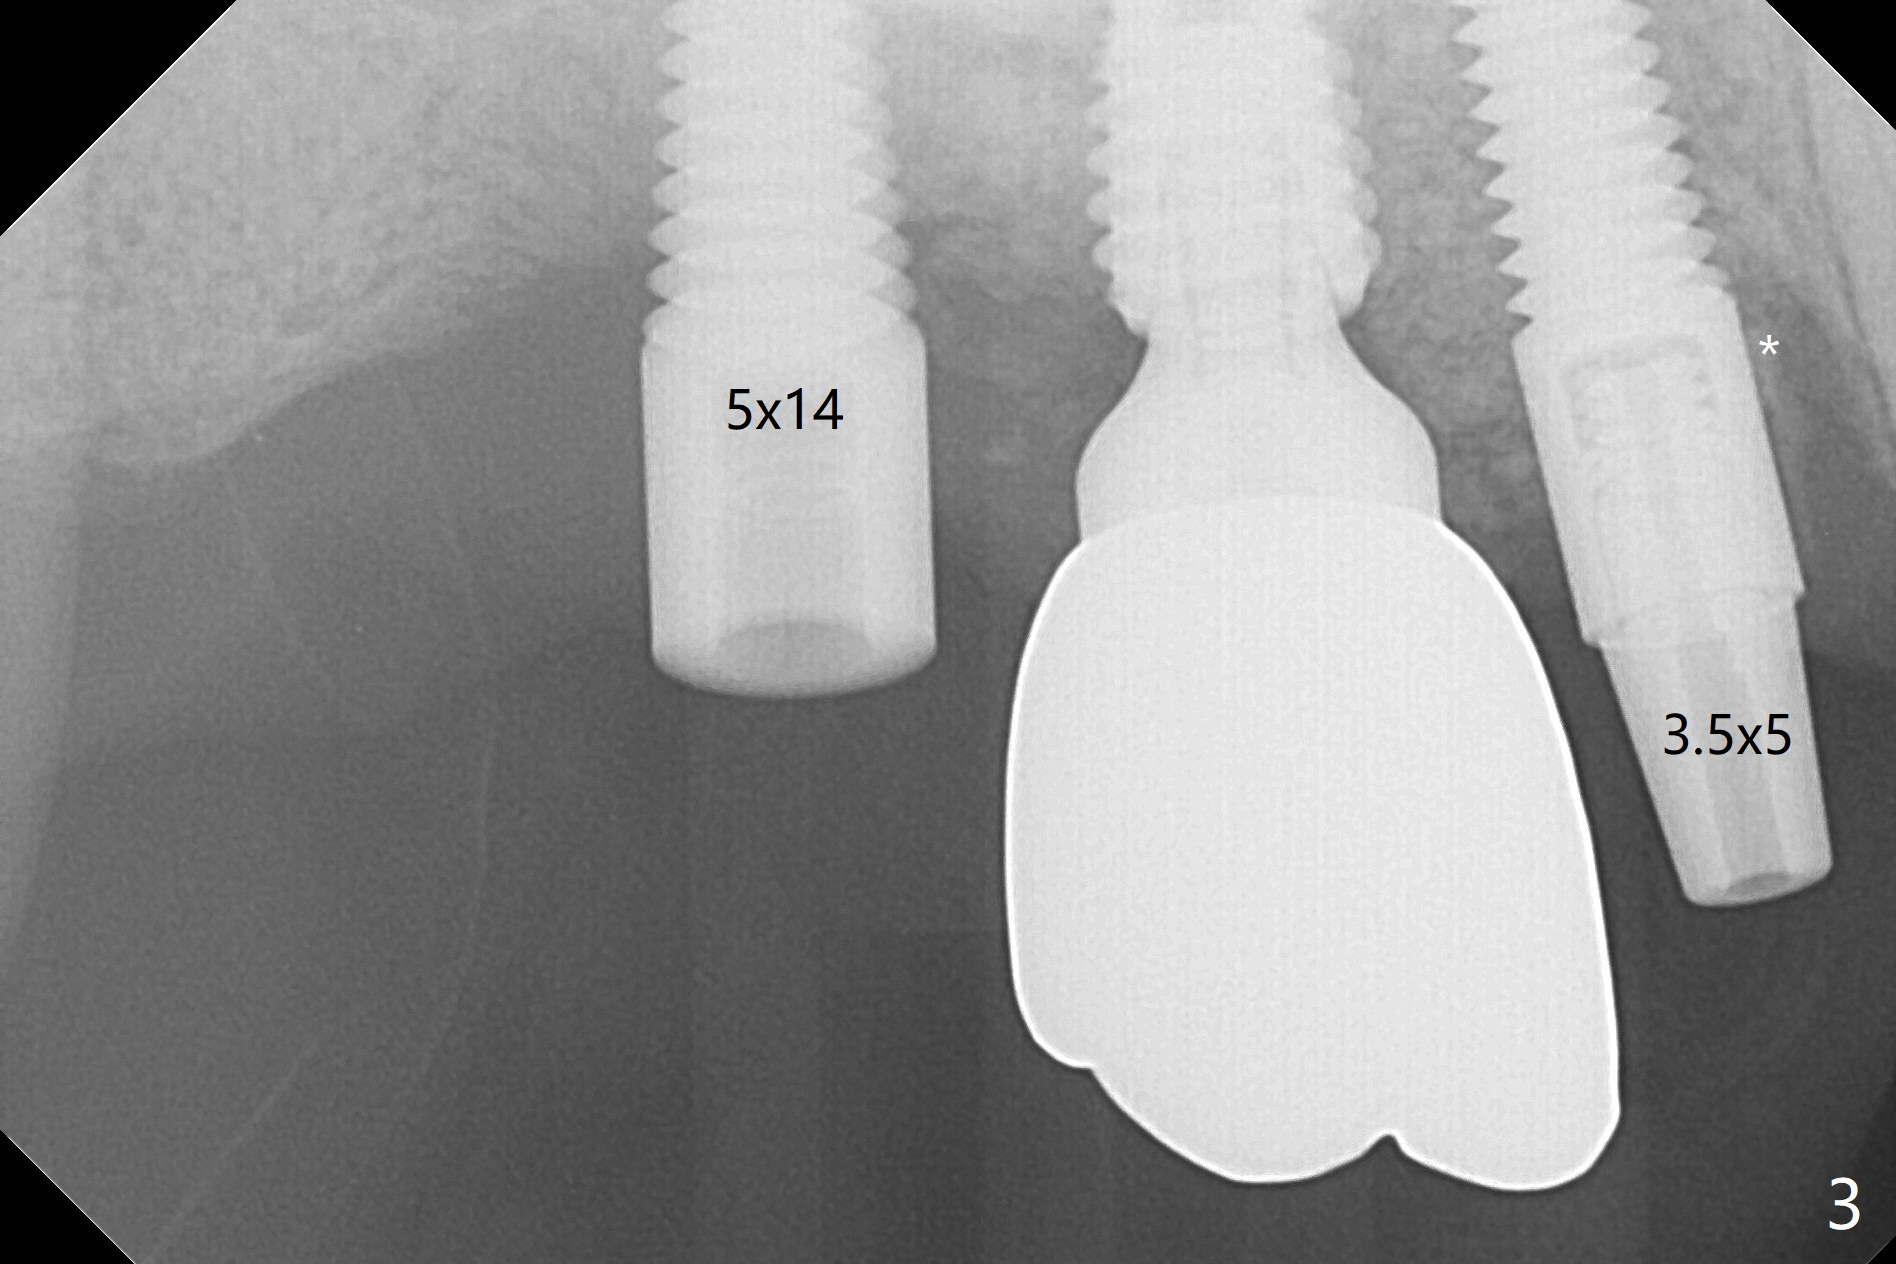

After osteotomy using bone-level implant guide at #4, the crown and abutment at #3 has to be removed to place a 4x14 mm tissue-level dummy implant because of the narrow space of #4 and implant placement angulation (Fig.1). Following initial placement of a final 4x17 mm implant and bone graft (Fig.2 *), the crown and abutment of #3 and the guide are reseated for correct implant trajectory. The guide has to be removed for final depth control. With the same mode, a 5x17 mm tissue-level tap is used at #2 following bone-level osteotomy with guide. A 5x14 mm tissue-level implant is placed with >50 Ncm (later placed deeper), while more bone graft is inserted mesial of #4 implant with a 3.5x5 mm abutment (Fig.3 *). Bone graft is introduced into the sinus using guided sinus lift kit (Fig.4,5 (CT sagittal and coronal sections)) * (D: distal, P: palatal)). The coronal half of the implant at #4 is covered by bone graft (Fig.6 *) buccal (B) and palatal within the deep socket. The implants at #2 and 4 seem to have osteointegrated nearly 5.5 months postop (Fig.7,8 (BW)). A 4.5x5 mm unipost is later placed at #2 with long chamfer margin. It appears that the abutment at #3 is wide. The hex is worn. It changes to a 5.5x7(4) mm one. After abutment adjustment for parallelism, a provisional FPD is fabricated. The latter will be adjusted for papilla formation between implants to reduce food impaction.